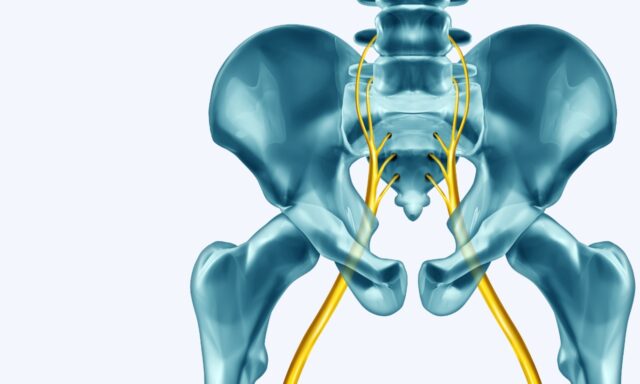

Síndrome Radicular Lumbar

Descripción

En este episodio nos acompaña Adam Dobson para hablar de todo lo relacionado con el síndrome radicular lumbar, desde su definición de la afección hasta el descarte de patologías graves y cómo trataría a los pacientes con síndrome radicular. También comparte su experiencia personal con el síndrome radicular lumbar.